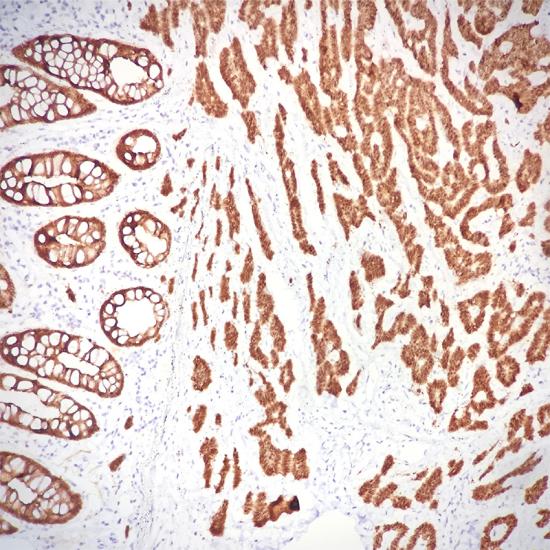

Villin標(biāo)記人結(jié)腸癌

絨毛蛋白是一種分子量為92.5kDa的細(xì)胞骨架蛋白,正常分布于腸上皮和腎近曲小管上皮,可用于腸上皮來(lái)源腫瘤與非腸上皮腫瘤的鑒別診斷,亦可作為胃腸道神經(jīng)內(nèi)分泌腫瘤診斷的參考指標(biāo)。